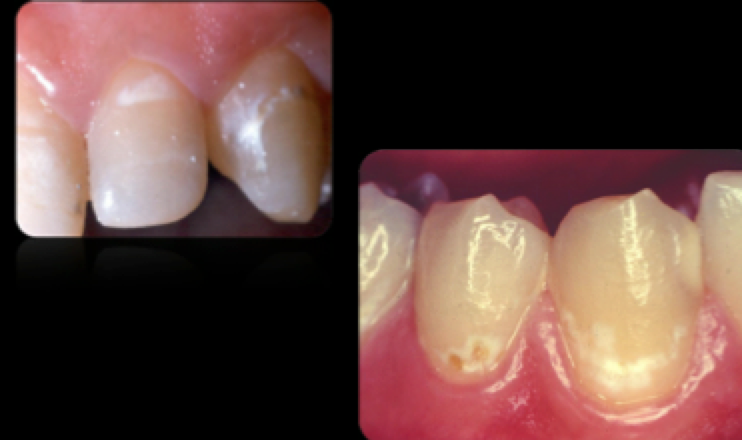

Active Lesion

Inactive Lesions

Inactive White Spot Lesion—–reversible & stable

Differential Diagnosis

—loss of tooth structure

Decalcification

Fluorosis